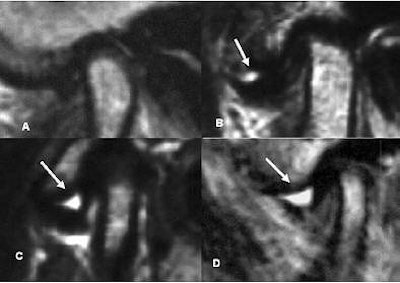

| Classification of "with" and "without" joint effusion. Arrows indicate joint effusion. (A) no effusion, (B) minimal effusion, (C) moderate effusion, (D) marked effusion. Panel A was without joint effusion. Panels B-D are examples with joint effusion. K Matsumoto, K Honda, K Sawada, T Tomita, M Araki, and Y Kakehashi. "The thickness of the roof of the glenoid fossa in the temporomandibular joint: relationship to the MRI findings," Dentomaxillofac Radiol 2006 35: 357-364. |

More specifically, there were 70 normal joints, 53 joints with ADWR, and 51 joints with ADWOR. The average minimum thickness of the RDF was 0.85 mm in normal joints, 0.90 mm in ADWR joints, and 0.93 mm in ADWOR joints.

Based on additional analysis, there were 21 joints with osteoarthritis (OA), 153 without OA, 61 with joint effusion, and 113 without joint effusion. The RGF thickness in the OA group was 0.99 mm versus 0.87 mm in the group without OA. RGF thickness in 33 joints with disk deformation was 0.87 mm compared to 0.89 in 141 joints without disk deformation.

However, there was a significant RGF thickness between the groups with joint effusion (0.97 mm) and those without joint effusion (0.84 mm), the authors stated, indicating that RGF thickness is influenced by joint effusion.

While the minimum thickness of the RGF in TMJ did not correlate with disk position or configuration, the increased RGF thickness in OA and joint effusion might indicate a relationship between that thickness and pain, which could be relevant clinical information for treatment planning, the authors stated.